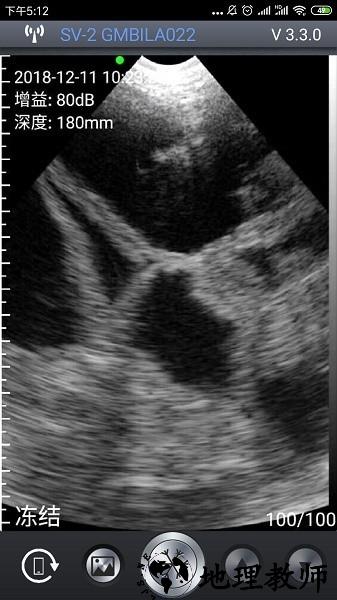

1、在进入APP后,屏幕左上角会显示当前时间、深度参数,若设备未连接或未启动探头,这些值将显示为--。

3、当探头正常工作且图像实时显示时,界面左上角会显示具体的增益,用户可据此调整图像清晰度与探测深度。

2、实时图像显示:即时呈现超声扫描画面,便于快速查看与初步判断检测结果。